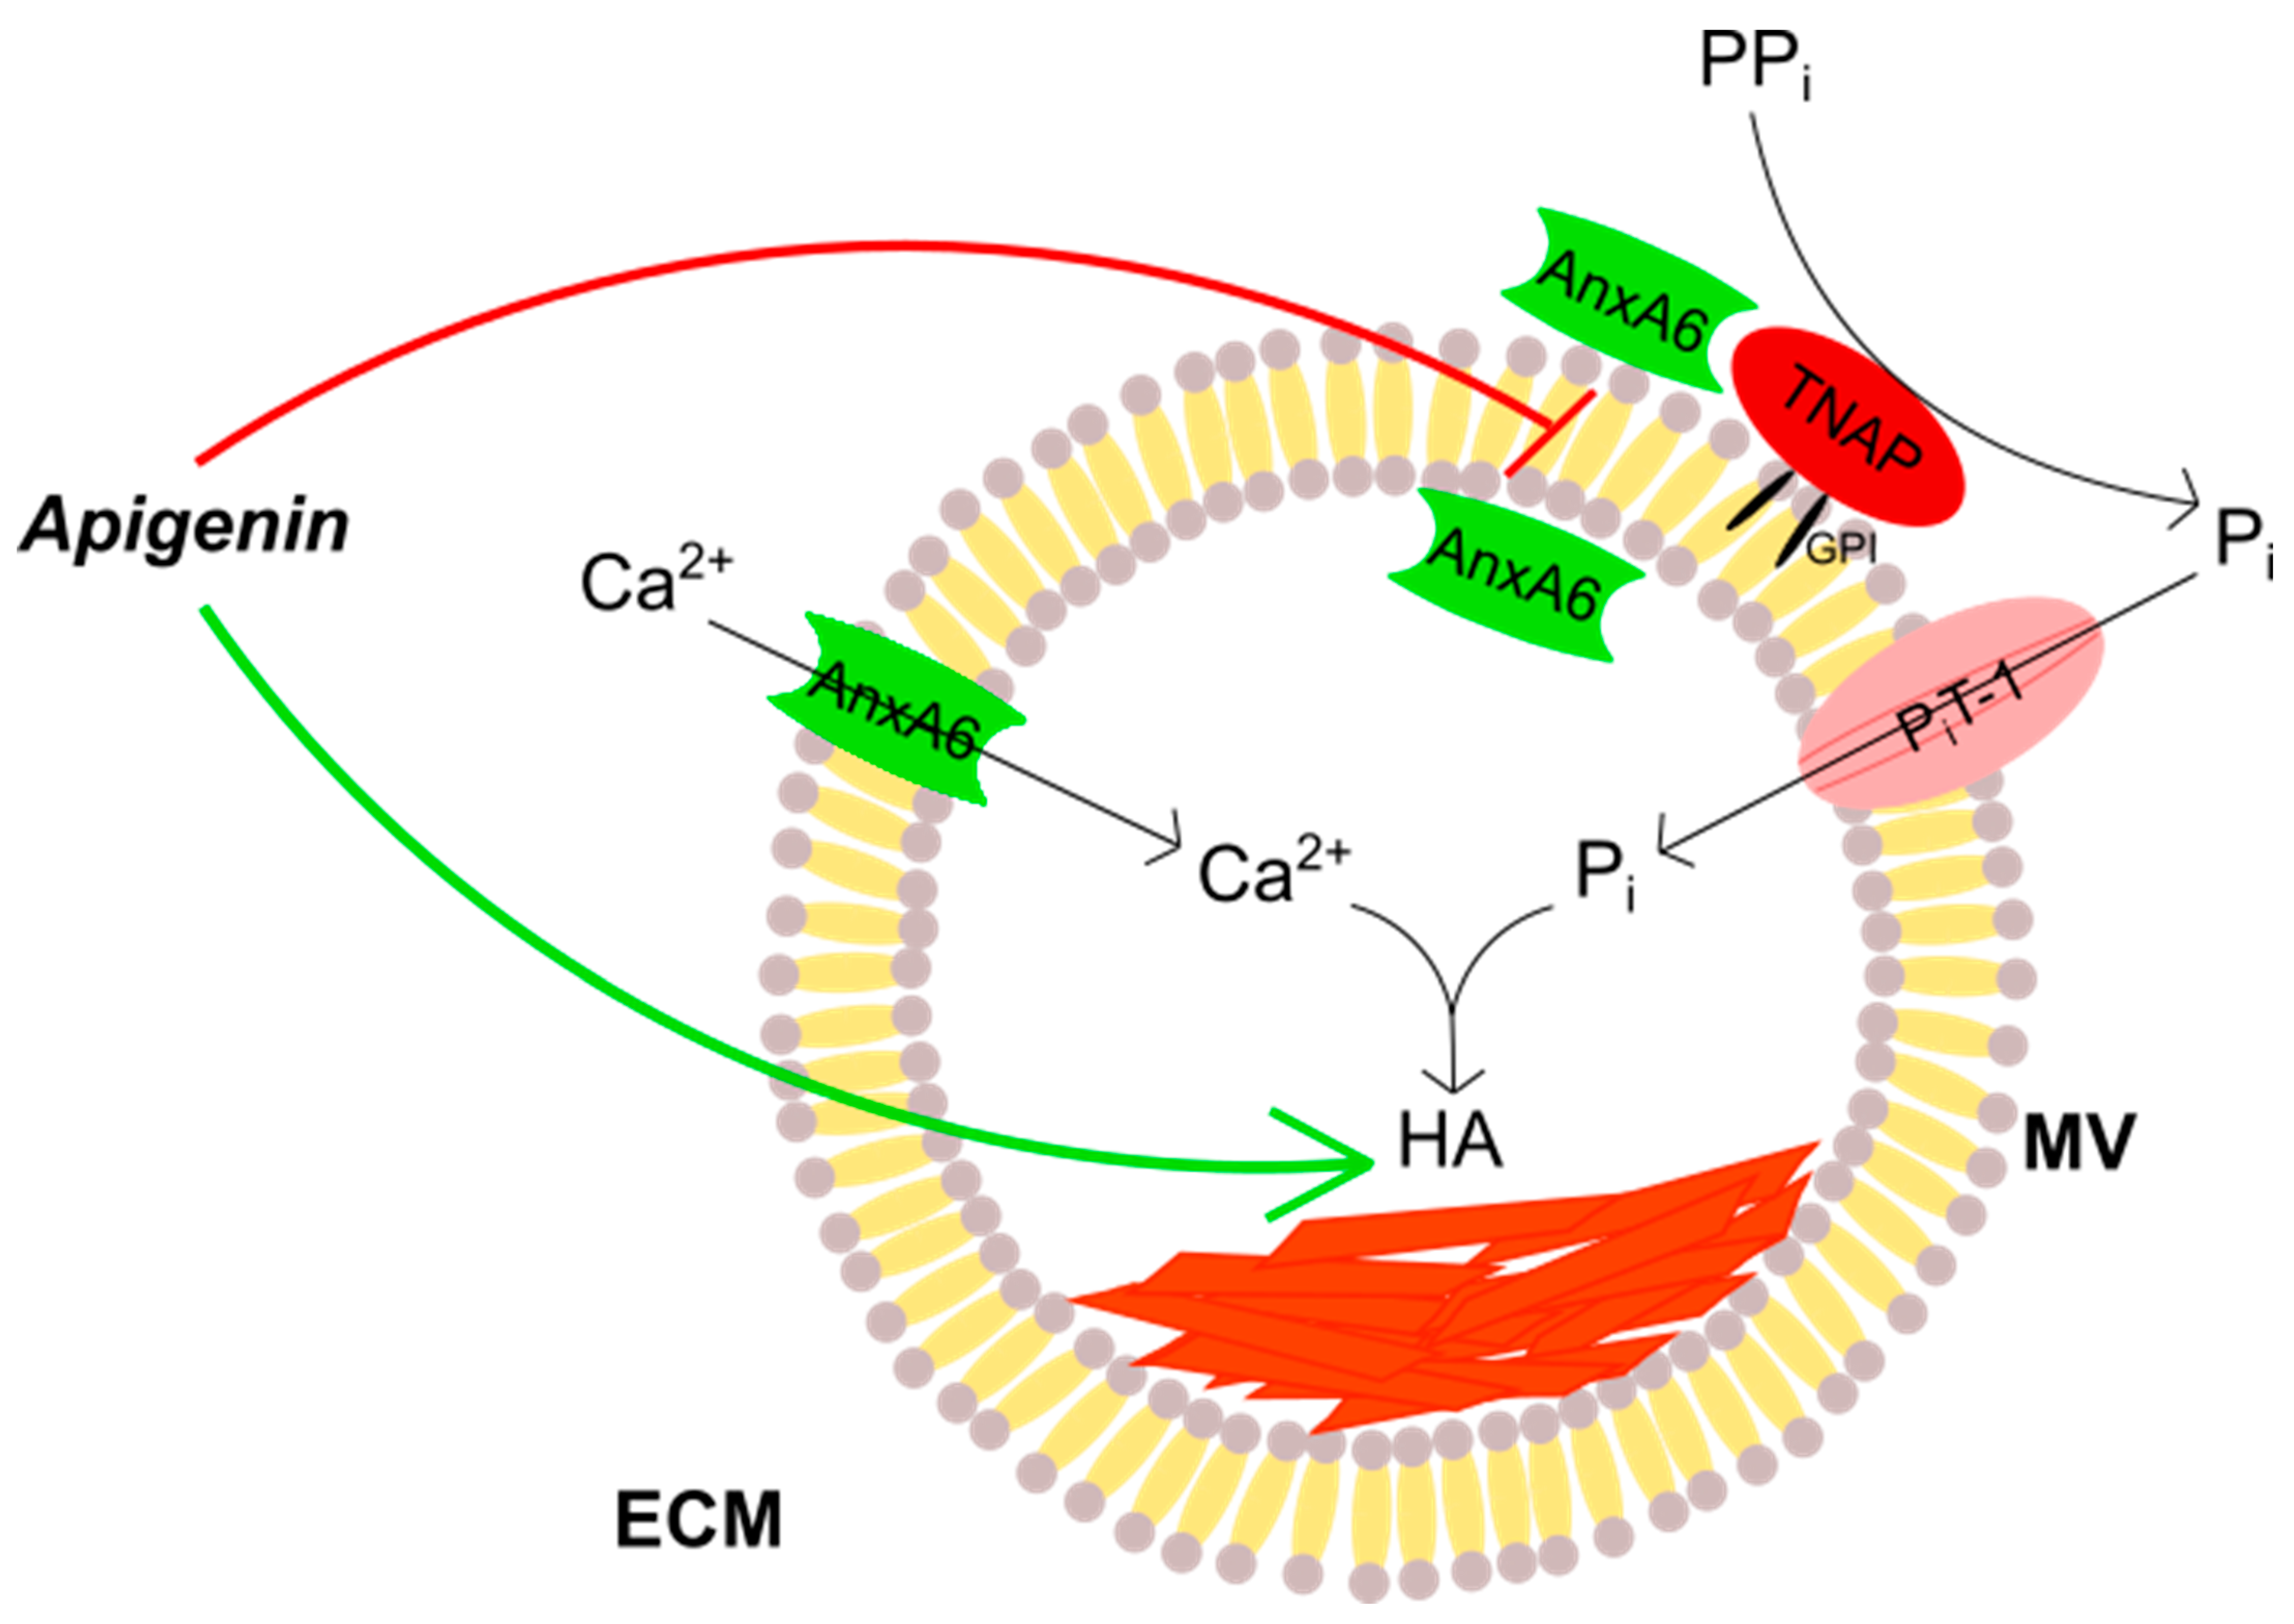

3. Discussion